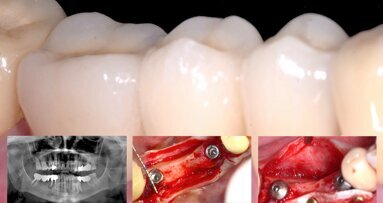

La cirugía se realizó bajo anestesia local (articaína 4 % con epinefrina 1:100000), se realizó la extracción de todos los dientes remanentes de forma atraumática (5,5, 5,4, 5,3, 1,1, 2,1, 6,3, 6,4, 6,5, 7,5, 7,4, 7,3, 8,3, 5,4, 8,5) y se colocaron 12 implantes inmediatos Phybo® de superficie TSA Avantblast (Impladent, Sentmenat, Barcelona, España) (6 en maxilar y 6 en mandíbula) (figura 4 y figura 5). En los implantes maxilares se combinaron fresas y osteotomos para preparar los lechos y en los implantes situados en la posición 5.5 y 6.5 se elevó el suelo del seno maxilar de forma atraumática mediante la utilización de osteotomos, elevando la membrana con ß-fosfato tricalcico (KeraOs®, Keramat, Santiago de Compostela, Spain) (figura 6 A y B).

Se evaluó la estabilidad primaria con el dispositivo de análisis de frecuencia de resonancia Osstell ISQ® (Integration Diagnostics AB, Gothengurg, Sweden); en todos los implantes se consiguió una estabilidad primaria superior a 60 ISQ, adecuada para realizar la carga inmediata.

Se atornillaron los postes de impresión y se reposicionaron los tejidos blandos suturando con seda 3/0 (Lorca Marin®, Murcia, España). Los postes se ferulizaron y unieron a la guía quirúrgica con resina acrílica autopolimerizable para provisionales (figura 7 A y B). Cuando la resina fraguó, se desatornillaron los postes para retirar la impresión y se colocaron pilares de cicatrización (figura 8).

Las prótesis fueron atornilladas a las 24 horas, con tornillos cortos de prótesis y con un torque de 15 N-cm (figura 9). Se comprobó la oclusión (máxima intercuspidación, lateralidades y protusión) para ajustar una oclusión mutuamente protegida con función de grupo. La adaptación marginal de la restauración se controló con una ortopantomografía (figura 10).

La prótesis definitiva se empezó a confeccionar a partir de las 8 semanas de la colocación de los implantes. A los 3 años de la carga se realizó un control clínico y radiográfico (figura 10) (figura 11).